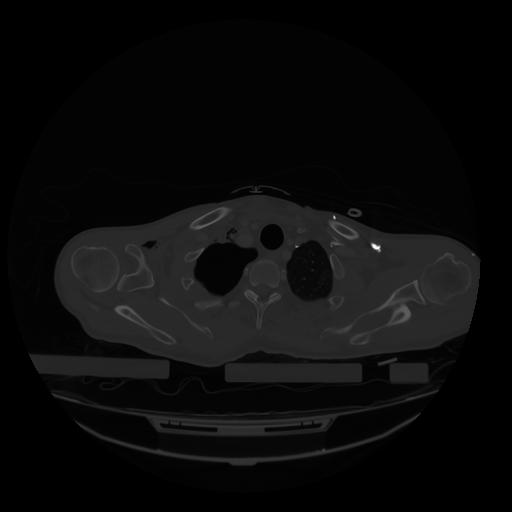

28 CUERPO,CE,Vol,2.0,CUERPO,,